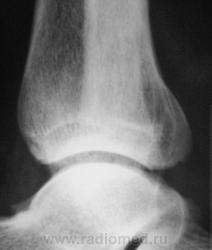

Пациент, в течение последних 2-х лет, жалуется на боли в нижней трети голени. Сегодня, хирургом, пациентка направлена на рентгенографию костей дистальной трети голени и голеностопного сустава. Что посоветуете уважаемые коллеги?

А что здесь советевать? Межберцовый неоартроз, вероятно, травматического генеза. Косой перелом н/л с признаками неполной консолидации. Попробуйте при производстве боковых снимков г/ст с-ва ( при травме) приподнимать пятку на 2-3 см.

Неоартроз между экзостозами? А что это за вздутие м/б кости на уровне неоартроза и пятнистость наружного кортикала? Следствие хронической воспалительной реакции?

Доброй ночи! Разволокнение коркового слоя, нечеткий очаг деструкции. Правда, нет секвестра. Если на увеличении не пригрезилось, то и линейный периостит. Вообще-то ответ был интуитивный, без логических обоснований. Ошиблась?

Какая-то непонятная структура костной ткани в области задней лодыжки.

Некоторая порозность, вероятно, нарушение трофики

В области внутренней лодыжки тоже пороз.